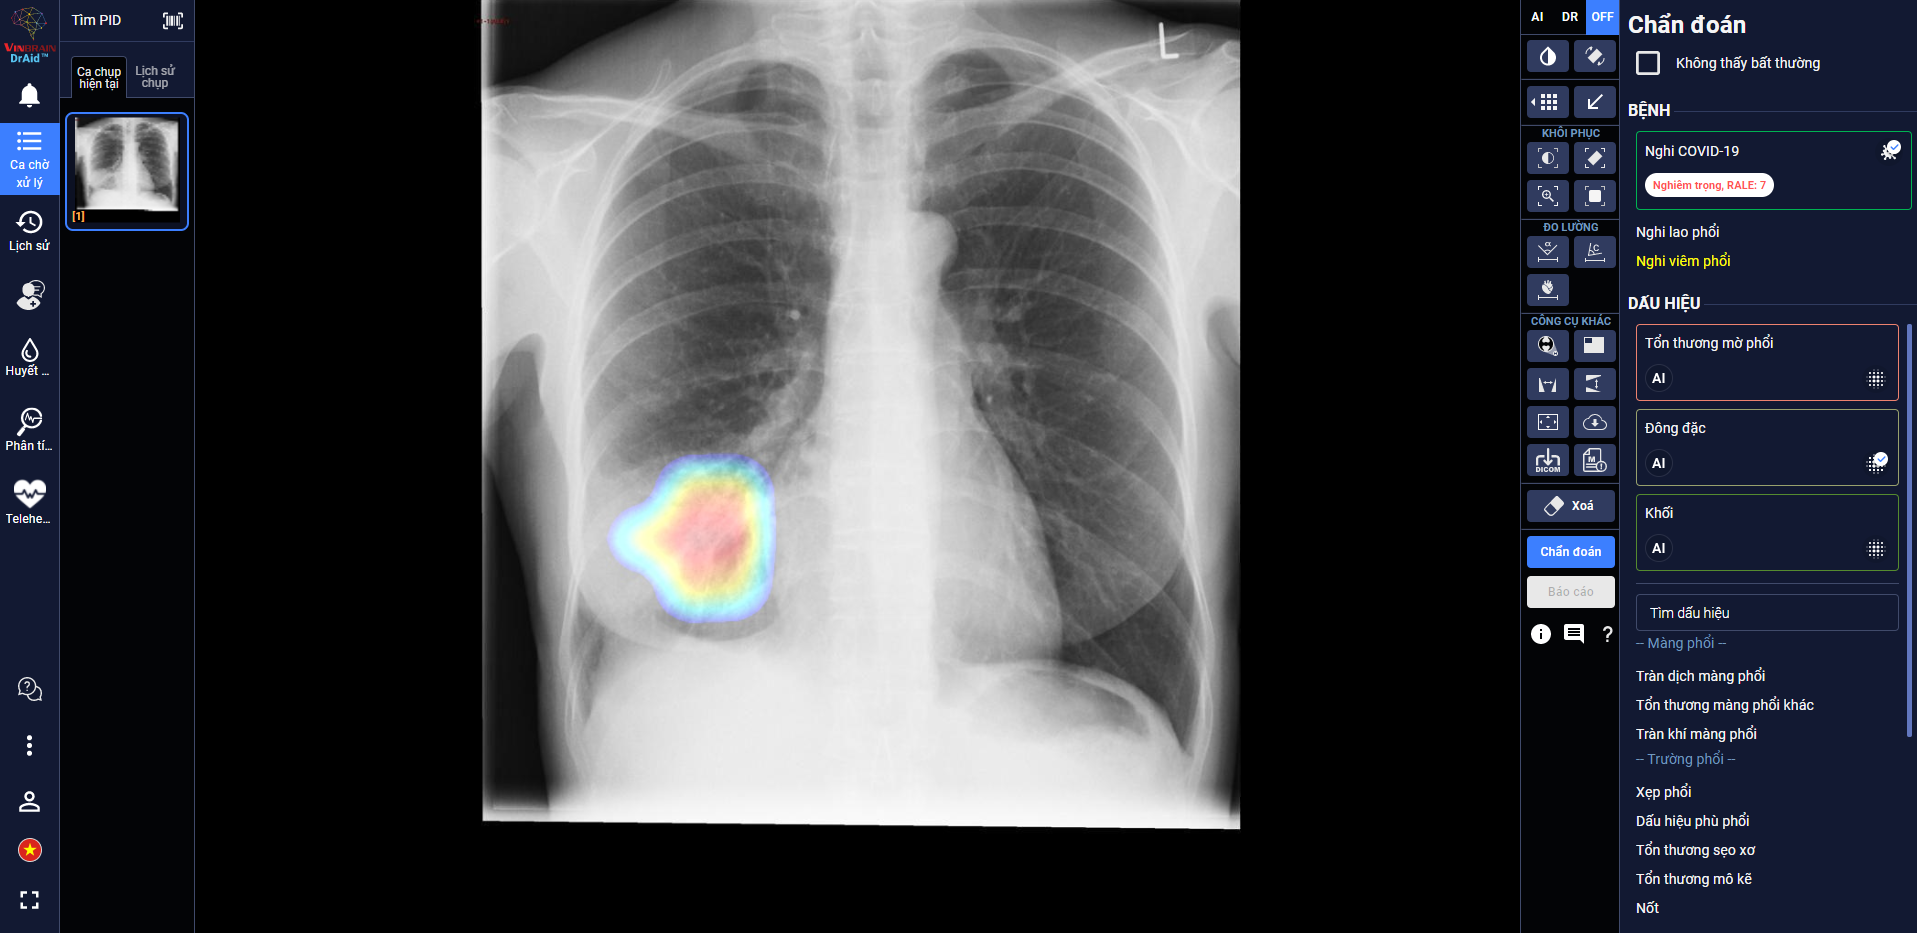

Sau hơn một năm nghiên cứu và phát triển, VinBrain vừa hoàn thiện sản phẩm DrAid cho Covid-19. Đây là công cụ có khả năng hỗ trợ chẩn đoán và tiên lượng điều trị dựa trên ảnh X-quang ngực thẳng.

DrAid giúp bác sĩ theo dõi mức độ tổn thương phổi ở một bệnh nhân F0 trên ảnh X-quang.

Trong các bệnh viện thu dung điều trị Covid-19, công cụ cũng giúp đội ngũ bác sĩ đánh giá mức độ tổn thương phổi của bệnh nhân qua từng ngày, từ đó đưa ra chỉ định điều trị kịp thời.